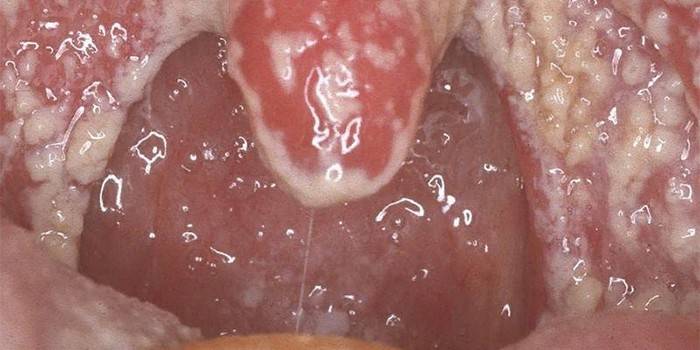

Esta forma de tonsilomicose é uma infecção fúngica de toda a faringe - a membrana mucosa do palato mole, cavidade oral, língua e arco. As manifestações clínicas da doença são ardor, secura, transpiração e dor agravada ao engolir. Neste contexto, há uma placa esbranquiçada ou amarelada na garganta. A faringomicose é mais grave que outras doenças inflamatórias da faringe.A causa da patologia é mais freqüentemente o fungo leveduriforme Candida, e em 5% dos casos - molde Geotrichum, Aspergillus, Penicillium.

O principal sintoma da doença é a placa, que pode cobrir não apenas as amígdalas, mas também toda a superfície da faringe, amígdalas e parede posterior. Tem uma tonalidade esbranquiçada se a candidíase for o agente causador e esverdeada se for mofada. Outros sintomas característicos de tonsilomicose:

- garganta vermelha.